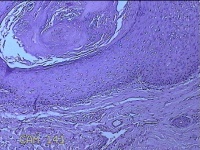

性别

男

年龄

45岁

临床诊断

皮下结节

一般病史

发现左侧一结节,伴局部瘙痒不适1年。

标本名称

左侧结节

大体所见

灰白暗红色带皮肤样结节0.8x0.7x0.3cm一个,表面糜烂,切开结节呈实性,切面灰白粉红色,质软。

图4

感觉像表皮样囊肿?